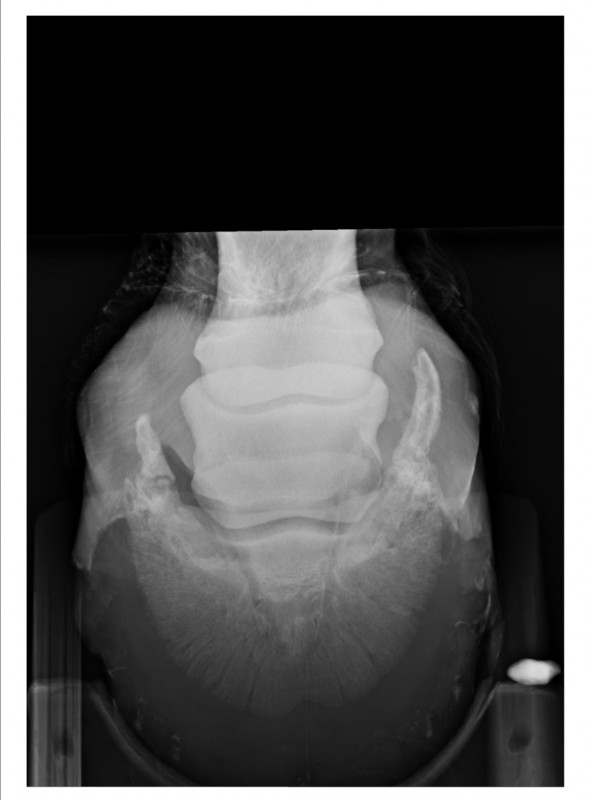

Résultat : arthrose en face antérieure de la 2ème phalange et ossification des cartilages ungulaires. D'après la véto, inutile de faire des radios de l'autre pied. Pour elle c'est sur qu'il y a la même chose, peut-être en moins développé mais présent quand même. C'est parait-il la "maladie des chevaux de trait"

marechal05 Oui j'ai fait des radios de l'antérieur droit en 2017 suite à une boiterie. La véto n'avait pas pensé nécessaire d'en faire de l'antérieur gauche qui d'après elle devait très certainement avoir les mêmes problèmes : arthrose sur la face antérieure de la 2ème phalange et ossification des cartilages ungulaires.

Antérieur droit Mars 2017

Antérieur gauche Septembre 2019